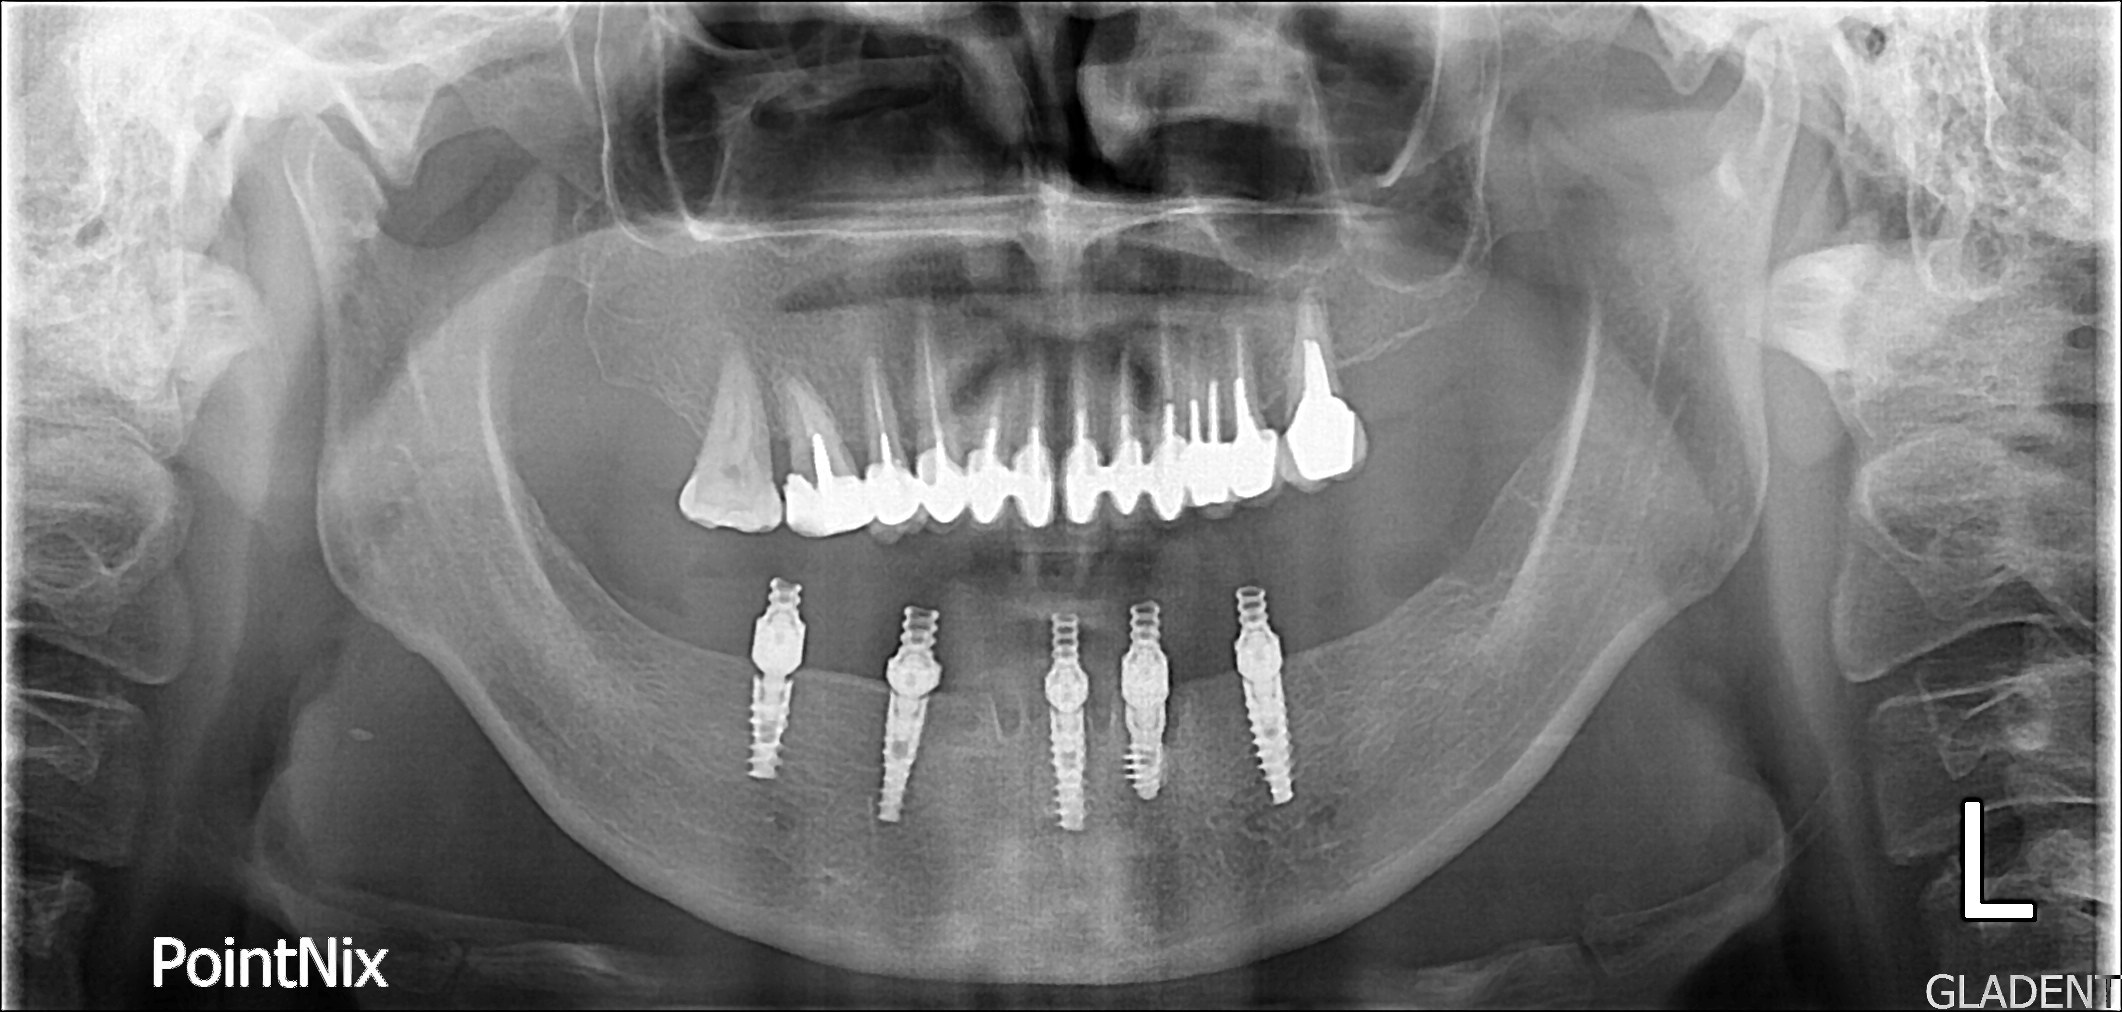

| КТ до имплантов |

КТ после

имплантации |